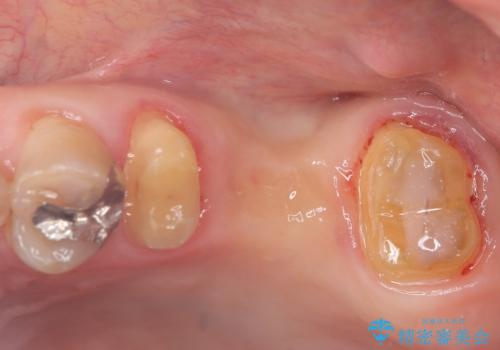

- 主訴:左上一番奥の歯の奥側にフロスを沿わせてこするといつも汚れがでてくる。

左上に保険適用の⑤ 6 ⑦ブリッジが入っており、7番目の歯と被せものとの境目に段差があり、そこに汚れが停滞したいたため適合の良いオールセラミッククラウンブリッジでのやり替えとなりました。

左上7番遠心マージン不適を認め、そこに汚れが停滞していたためやり替えをおすすめし、汚れが付着しずらく審美性に優れたセラミッククラウンブリッジでのやり替えとなりました。

保険適用のメタルインレーを除去したところ、ポンティック部の過度な加圧によって歯肉が強く発赤していたため、一度仮歯に置き換え歯肉の治りを待った後、適切な加圧強さのオールセラミッククラウンブリッジをセットしています。